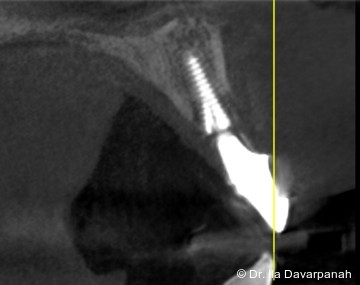

Postoperativ kam es trotz korrekter Implantatpositionierung und regelrechter Sofortversorgung zu einer Fraktur des Implantatkörpers im Bereich der Implantatschulter. Die radiologische Diagnostik mittels Röntgen und DVT zeigte ein Aufplatzen des Implantats im Übergangsbereich zwischen Konusverbindung und Implantatplattform. Das Frakturmuster deutete auf eine strukturelle Überlastung im hoch beanspruchten Schulterbereich hin. Implantatfrakturen stellen insgesamt eine seltene, jedoch für Patient und Behandler belastende Komplikation dar. Sie treten bevorzugt in Regionen mit erhöhten Biege- und Querkräften auf, insbesondere in der Frontzahnregion und bei frühzeitiger funktioneller Belastung.

Im vorliegenden Fall lag der Fokus der Analyse weniger auf der chirurgischen Umsetzung oder der Indikationsstellung, sondern auf der mechanischen Belastbarkeit. Der Schulterbereich eines Implantats ist biomechanisch besonders exponiert, da hier funktionelle Kräfte konzentriert eingeleitet werden. Unterschiedliche konstruktive Ansätze versuchen, diese Belastung durch Modifikationen der Verbindung oder der Kraftübertragung zu reduzieren. Insbesondere bei Sofortimplantationen mit Sofortversorgung ergeben sich erhöhte Anforderungen an die mechanische Reserve des Systems.